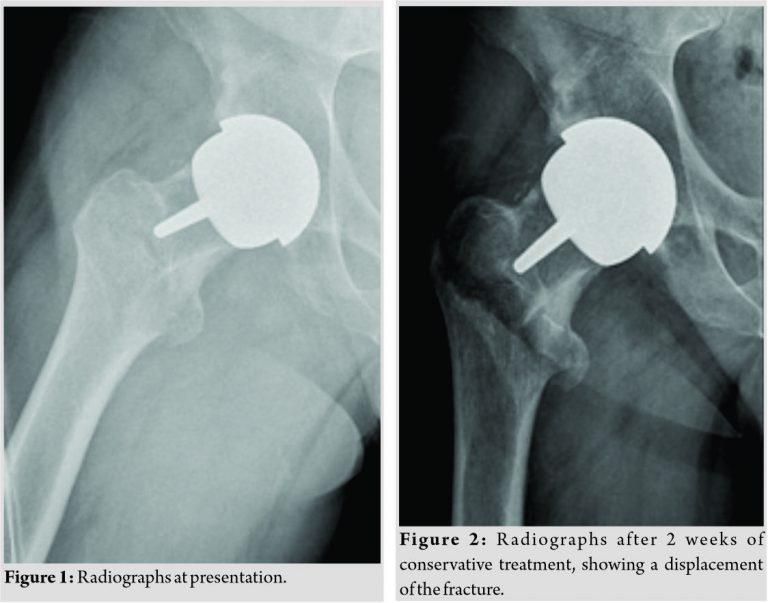

A 46-year-old-man was admitted to our emergency department after a fall from his own height. Two years earlier, he had undergone a resurfacing arthroplasty (Cormet, Corin Group, Cirencester, UK) of the right hip following avascular necrosis of the femoral head. The recovery from the arthroplasty had previously been uneventful, and post-operative radiographs revealed satisfactory positioning of the implants. Three months before the admission in our institution, the patient suffered a motorcycle injury and was diagnosed with a talus fracture, which was treated conservatively. On admission in the emergency department, the patient complained of severe pain in the right hip and was unable to stand. Radiographs showed a closed intertrochanteric fracture, AO 31-A2 (Fig. 1). In our opinion, disuse osteopenia following the conservative treatment of the talus fracture might have contributed to an increased fracture risk. After consideration of the management options and discussion with the patient, and with regard to the minimal displacement of the fragments, a conservative treatment was undertaken. A skin traction of 3kg was applied. Ten days after the admission, control radiographs revealed a significant displacement of the fragments (Fig. 2).